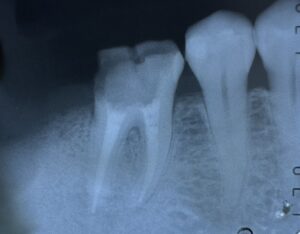

根管充填 後 の レントゲン所見 です。

マイクロスコープ が あります から

根管治療

随分と 楽に なりました。

近心頬側根管 は 根管充填 して ません。

亀裂が

ヤハリ

ありました。

次回

この 根管に ついては

外科手術 にて 対応 する 予定です。